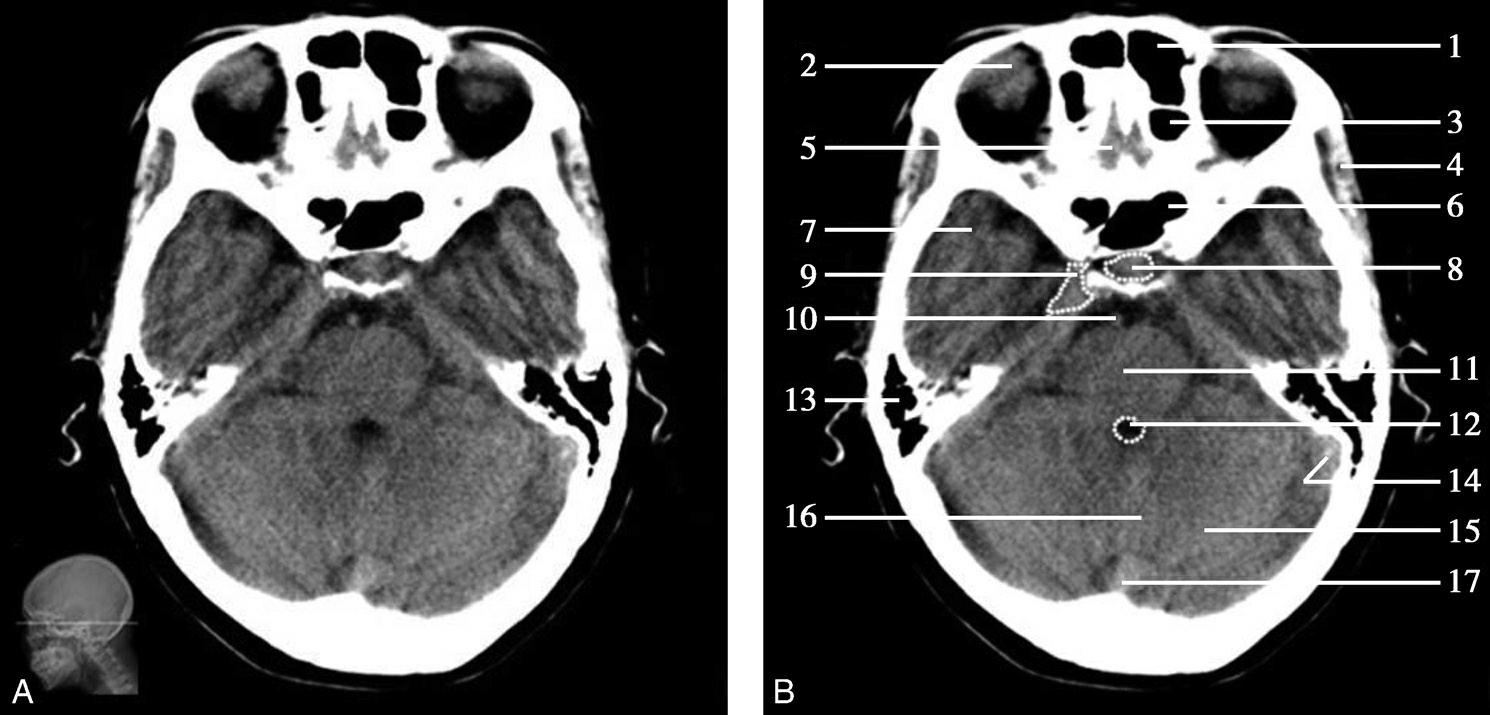

重要结构:卵圆孔、棘孔、破裂孔、斜坡、颞骨岩部、颈静脉孔(图1-2-1、图1-2-2)。

图1-2-1 颅底层面

A.横断面;B.横断面标注

1.晶状体;2.筛窦;3.颞肌;4.中颅窝底;5.外耳道;6.延髓;7.乙状窦;8.小脑半球;9.眼球;10.眼眶;11.上颌窦;12.蝶窦;13.乳突;14.耳郭;15.小脑蚓部;16.枕内隆凸

图1-2-2 颅底层面(骨窗)

1.鼻骨;2.筛窦纸板;3.颧骨眶突;4.翼腭窝;5.蝶骨大翼;6.卵圆孔;7.破裂孔;8.颞骨颧突;9.棘孔;10.斜坡;11.颞骨岩部;12.乳突;13.颈静脉孔;14.枕乳突缝;15.枕骨;16.枕内隆凸

层面前部呈开口向前的“V”字形,正中为鼻中隔,向两侧依次为筛窦和眼眶,眼眶内前部为眼球,后部为眶脂体。翼腭窝位于眼眶后部,窝内含有脂肪并有上颌神经通过。层面中部为蝶骨体,蝶骨体中部可见含气蝶窦,蝶窦后方为枕骨基底部,两者呈前后关系,其上面构成斜坡。蝶窦两侧为蝶骨大翼,其后外侧缘处由前向后可见卵圆孔和棘孔,分别有下颌神经和脑膜中动脉通过。斜坡外侧、岩骨尖前方为破裂孔。蝶骨大翼与眶外侧壁的颧骨借颧弓相连,颧弓和蝶骨大翼之间有咬肌及颞肌。层面中部外侧为外耳道。颞骨岩部呈“八”字形,相互之间借破裂孔软骨、蝶岩软骨结合和岩枕软骨结合连接。岩部后外侧的乳突部内可见乳突小房,乳突部与枕骨相接。岩骨后部可见颈静脉孔,内有颈内静脉、舌咽神经、迷走神经和副神经通过。层面后部为颅后窝,其内可见延髓,延髓前方为延髓前池,内有椎动脉,后外侧为小脑半球下部,后方为第四脑室、小脑扁桃体及小脑蚓部。

破裂孔、卵圆孔、棘孔及斜坡等均为重要的解剖结构,临床常见疾病如鼻咽癌常侵犯上述结构(图1-2-3)。颈静脉孔区较常见的肿瘤为颈静脉球瘤,常伴有颈静脉孔及其邻近骨质的破坏(图1-2-4)。